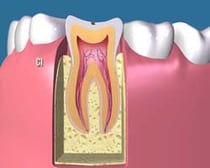

C1:

c1

歯の表面に穴が少し開いて、表層のエナメル質に限局して虫歯に犯されている状態です。まだ症状が全く出ない状態です。レジン治療が適応となります。